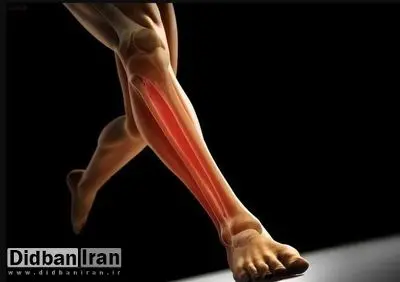

شین اسپلینت به دردهایی گفته میشود که در امتداد استخوان ساق پا یا درشتنی (تیبیا) احساس میشوند. استخوان تیبیا، استخوان بزرگی است که از زیر زانو شروع میشود و تا جلوی بخش پایینی ساق پا امتداد دارد. درد معمولاً در جایی ایجاد میشود که عضلات به استخوان ساق پا متصل میشوند. این عارضه زمانی شایع است که تمرینات ورزشی به شکل مکرر و با فشاری زیاد روی پاها انجام شود

به گزارش سایت دیدهبان ایران، شین اسپلینت به دردهایی گفته میشود که در امتداد استخوان ساق پا یا درشتنی (تیبیا) احساس میشوند. استخوان تیبیا، استخوان بزرگی است که از زیر زانو شروع میشود و تا جلوی بخش پایینی ساق پا امتداد دارد. درد معمولاً در جایی ایجاد میشود که عضلات به استخوان ساق پا متصل میشوند. این عارضه زمانی شایع است که تمرینات ورزشی به شکل مکرر و با فشاری زیاد روی پاها انجام شود.

وارد آوردن فشار مکرر از طریق فعالیتهایی مانند دویدن با کفشهای نامناسب یا بدون حمایت کافی، میتواند منجر به دردناک شدن شین اسپلینت شود. این درد ممکن است در امتداد یا در دو طرف استخوان ساق پا احساس شود.اگر دچار شین اسپلینت باشید، ممکن است پزشک شما آن را با نام «سندرم استرس تیبیای میانی» نیز معرفی کند. این نام دیگرِ التهابی دردناک است که به دلیل فشار بیشازحد به عضلات، تاندونها و استخوان ساق پا ایجاد میشود.